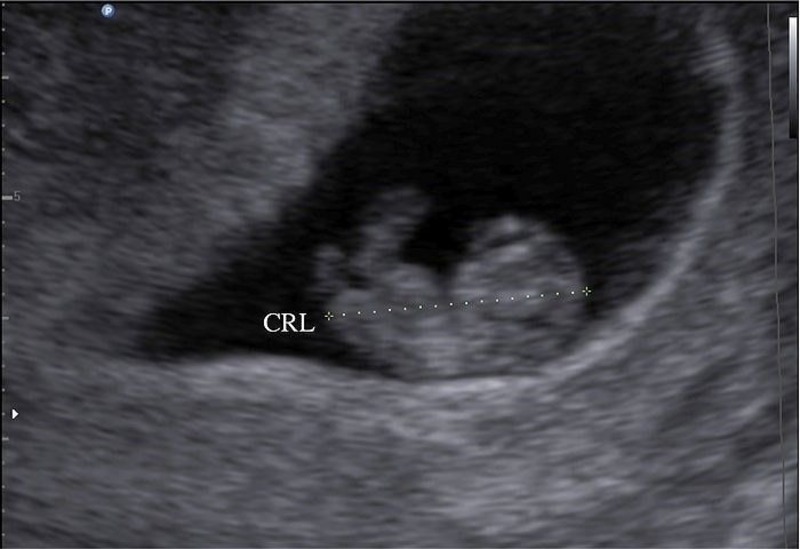

Chỉ số CRL (Crown Rump Length) là chỉ số đo chiều dài từ đỉnh đầu (crown) đến mông (rump) của thai nhi, được sử dụng phổ biến trong siêu âm thai ở giai đoạn 3 tháng đầu (từ tuần 6 đến tuần 14 của thai kỳ). Đây là giai đoạn mà thai nhi có hình dạng tương đối rõ ràng và cơ thể chưa duỗi dài hoàn toàn, nên việc đo chiều dài từ đầu đến mông giúp bác sĩ ước tính chính xác tuổi thai và sự phát triển ban đầu của em bé.

CRL được coi là thông số đáng tin cậy nhất để xác định tuổi thai trong giai đoạn đầu, vì sự phát triển của thai nhi lúc này diễn ra đồng đều và ít bị tác động bởi các yếu tố bên ngoài. Ngoài việc xác định tuổi thai, chỉ số CRL còn giúp bác sĩ phát hiện những bất thường trong quá trình phát triển ban đầu của thai nhi và dự đoán ngày dự sinh với độ chính xác cao.